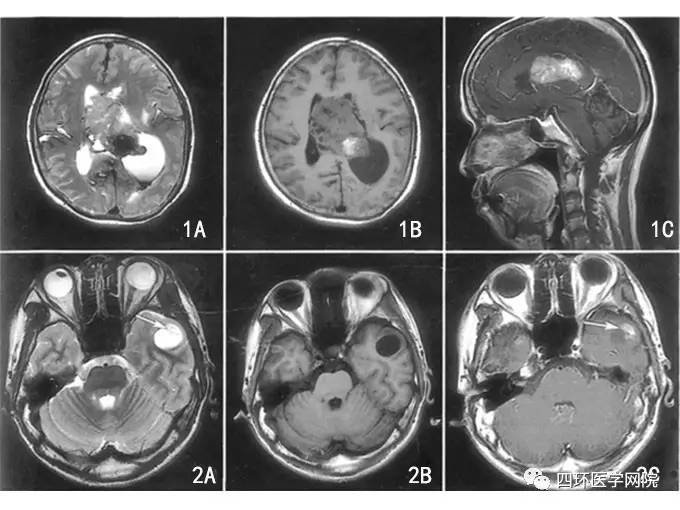

DNT在MRI T1加权像上表现为低信号,在MRI T2加权像上表现为高信号。病灶基于皮质,并局部扩张皮质,有时会延伸入白质。增强表现各异,发生于不到1/2的病例;增强为斑片状、多灶性,而非弥漫性增强。因肿瘤生长缓慢,邻近病灶的颅骨有时变形。

图:DNET磁共振表现